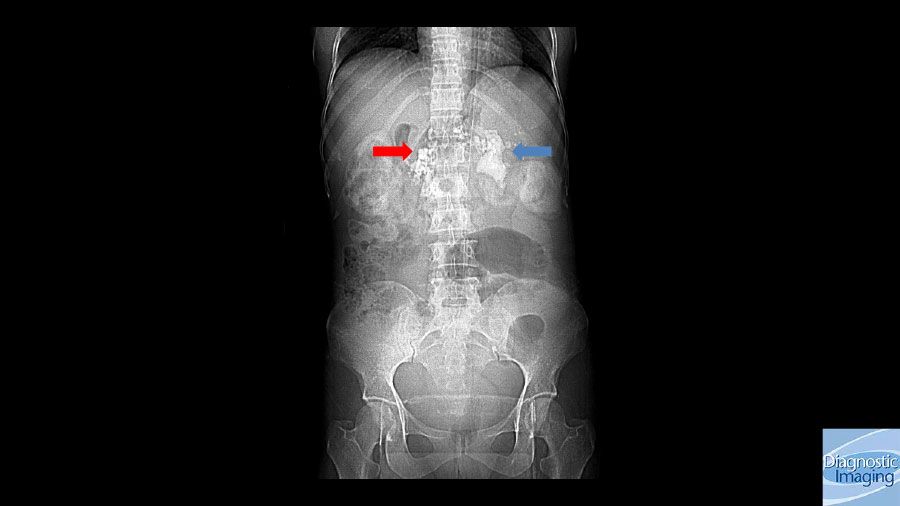

Case History: 40-year-old female presented with history of epigastric fullness associated with epigastric and left flank pain and burning micturition.

Case History: 40-year-old female presented to emergency room with history of epigastric fullness for one month, associated with epigastric and left flank pain and burning micturition.